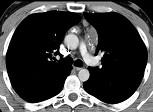

问题 21岁,女,颈部淋巴结肿大,无压痛,请结合CT检查,选出最可能的诊断 ( )

选项 A.淋巴瘤 B.淋巴结核 C.结节病 D.转移性淋巴结肿大 E.间皮囊肿

答案 A